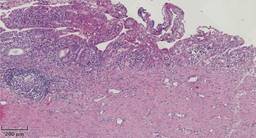

Se envía el quiste a patología para su valoración, encontrando los siguientes hallazgos: una pared del quiste compuesta por tejido fibroconectivo denso, revestido por epitelio cilíndrico simple acompañado de infiltrado inflamatorio agudo y crónico. Una lámina propia con vasodilatación e infiltrado agudo y crónico que se extiende a la pared del quiste. Hiperplasia papilar focal de la mucosa e incluso áreas de ulceración focal y una formación de un folículo linfoide secundario (Figura 6).

Figura 6: Laminilla. Hiperplasia papilar focal de la mucosa, con infiltrado inflamatorio crónico y agudo, áreas de ulceración focal. Formación de un folículo linfoide secundario.